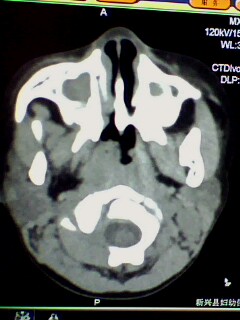

标题: PED3023:鼻咽增殖体肥大。

男,3岁小儿,经常睡觉时张口呼吸、打鼾。

2、双上颌窦应该有炎症了吧,听好多人说,小孩副鼻窦还没发育完全也可有这种表现,究竟两者怎样鉴别?请各位战友指点。多谢

特别关心这一例,是上颌窦炎还是发育不完全?

两者怎样鉴别?请各位老师指点,多谢!

1)鼻咽腺样体肥大。2)双侧上颌窦、双侧筛窦及双侧蝶窦炎症。